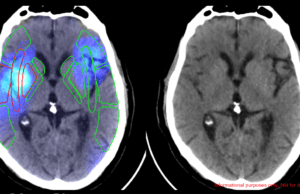

Viz.ai announces integration of Avicenna.AI’s CINA-ASPECTS stroke severity assessment tool

Leading artificial intelligence (AI)-based medical imaging companies Viz.ai and Avicenna.AI have announced the integration of Avicenna.AI’s CINA-iPE and CINA-ASPECTS tools into Viz.ai’s One platform....

Avicenna.AI announced today that it has received 510(k) clearance from the US Food and Drug Administration (FDA) for its CINA-ASPECTS and CINA-iPE products.

CINA-ASPECTS is...

Avicenna.AI receives CE mark for AI tool to assess stroke severity

Medical imaging AI specialist Avicenna.AI has received CE mark certification for its CINA ASPECTS AI tool for stroke severity assessment. CINA ASPECTS automatically processes...